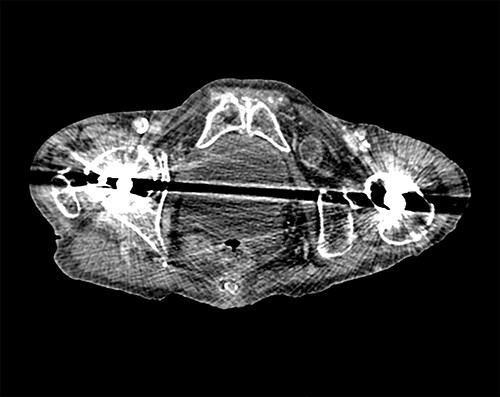

Following surgical review, a computerized tomography (CT) scan of the abdomen and pelvis was requested and showed small bowel obstruction, secondary to a left-sided obturator hernia (Figs 1 and 2).

Coronal view CT scan with IV contrast showing dilated small bowel loops and bowel loop through the left obturator canal.